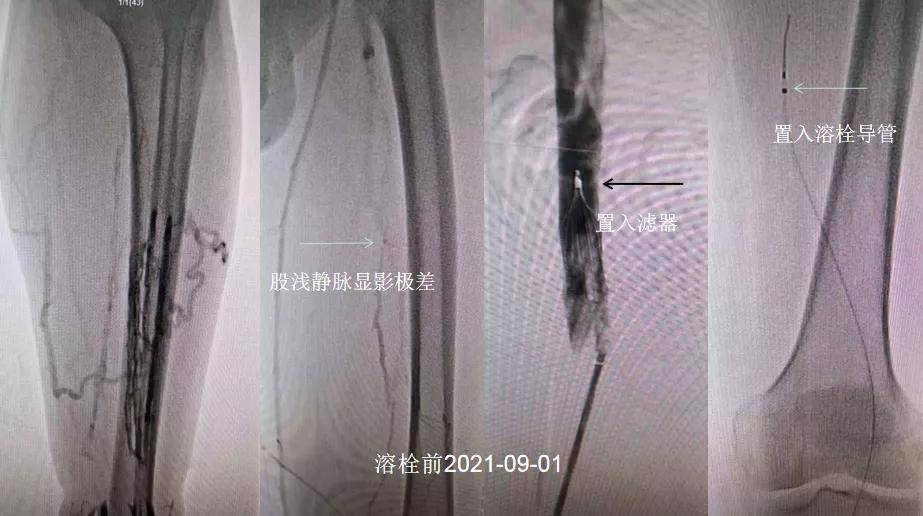

首次术前术中

外科毛雪飞、李宝钢两位医师首先穿刺患者左侧足背静脉 , 进行左下肢静脉顺行造影 , 提示左下肢深静脉显影差;再穿刺右侧股静脉 , 置入滤器;最后穿刺胫前静脉 , 置入溶栓导管 , 首次手术顺利结束 。